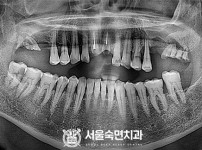

임플란트-전후사진1

임플란트-전후사진2

임플란트-전후사진3

임플란트-전후사진4

임플란트-전후사진5

임플란트-전후사진6

치과를-선택할-때-꼭-확인하세요-서울숙면치과-임플란트-전후사진